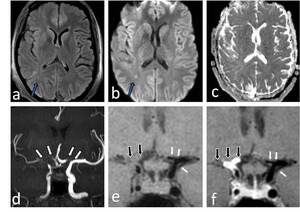

Neuroradiology

ORIGINAL PAPER

High-grade gliomas associated with neurofibromatosis type 1: analysis of imaging features and literature review

Pol J Radiol, 2025; 90: 458-464